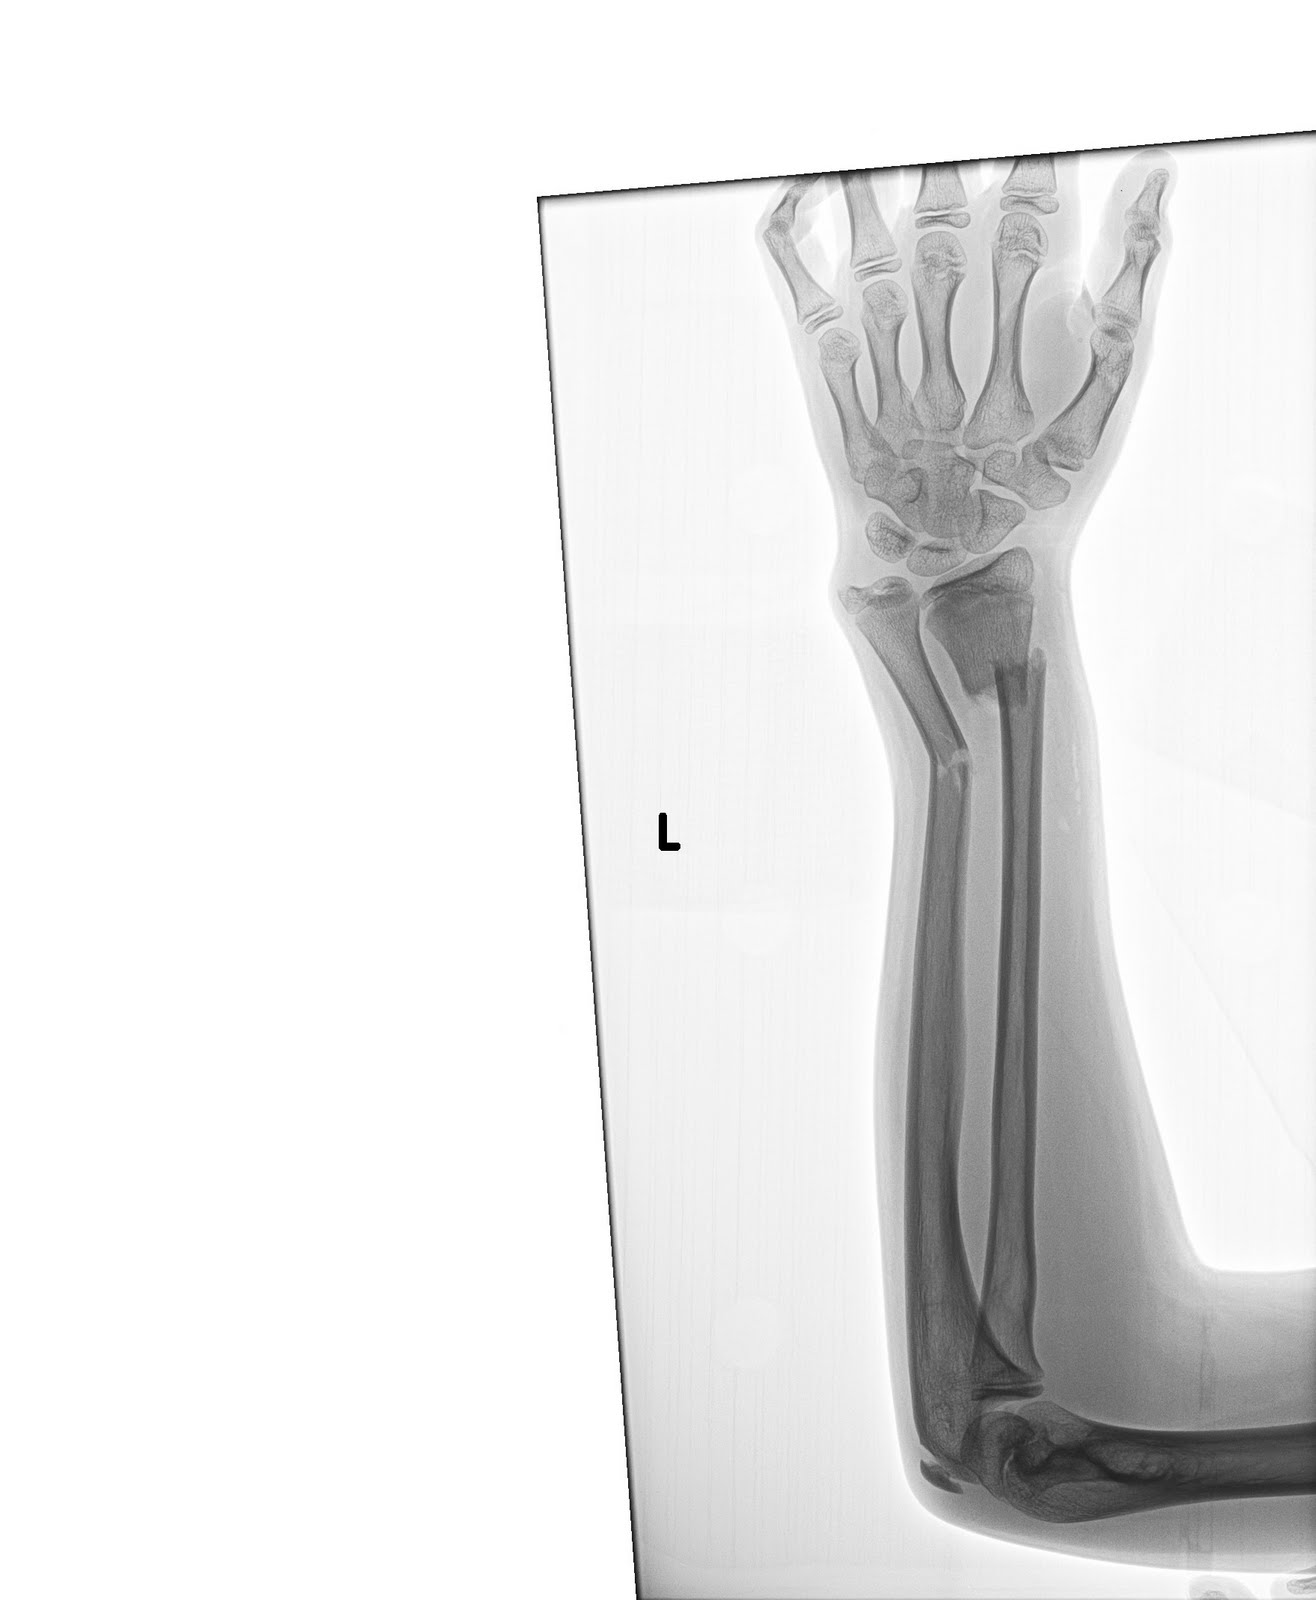

The original x-ray… ouch!

July 23, 2011 at 6:35 amAwesome cast!! And Ouch is right looking at that xray.